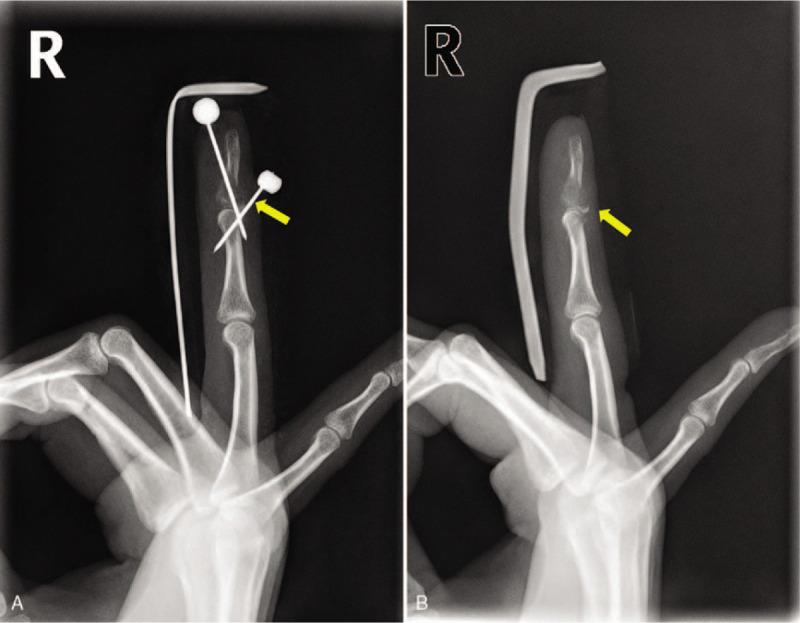

We performed a operation, involving curettage and bone grafting. Complete removal of the lesion was confirmed intraoperatively with the image intensifier, and the cavity was irrigated and subsequently filled with allogenous bone and demineralized bone matrix.

我们进行了手术,包括刮除和植骨。术中通过影像增强器确认病变已完全切除,对骨腔进行冲洗,随后用异体骨和脱矿骨基质填充。